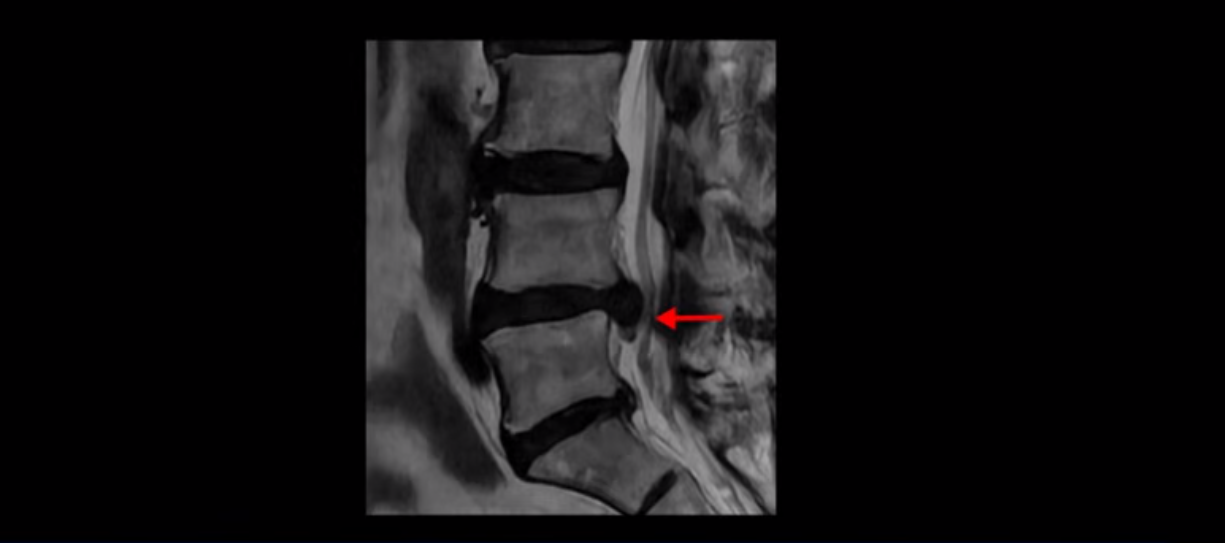

이분 MRI를 먼저 보실까요. 보시다시피 척추 여러 마디가 퇴행되어 있고

4번 5번 마디에는 심한 디스크 파열이 있습니다.

밀려 나온 수핵이 밑으로 흘러내려가 있는데, 이분의 증상은 급성 디스크 증상은 없고 협착증 증상이라서 이 디스크 파열은 오래전에 발생해서 이미 밀려 나온 수핵이 흡수되지 않고 굳어있는 상태로 보입니다.

단면을 보면 디스크 수핵은 왼쪽으로 심하게 밀려 나와 있고

좌우 뒤쪽에는 황색 인대가 두꺼워져 있습니다.

앞에서는 디스크 수핵이 신경 공간으로 침범하고 뒤에서는 두꺼워진 인대가 신경 공간을 좁히고 있습니다.

이렇게 신경 공간이 좁아진 것을 협착이라고 합니다. 왼쪽으로 신경 구멍이 더 좁아져 있으니까 처음에는 왼쪽 엉덩이와 다리가 아팠는데 몇 년 동안 주사 맞으면서 버티다 보니까 오른쪽 다리까지 아프게 됩니다. 결국 양쪽 다리가 너무 아파서 5분 걷기도 힘들어지게 됩니다.